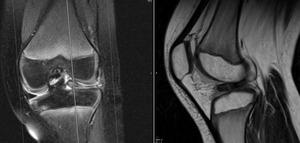

A MRI of the knee revealed a displaced tear of the anterior and posterior horns of the lateral meniscus (Figures 2 & 3).